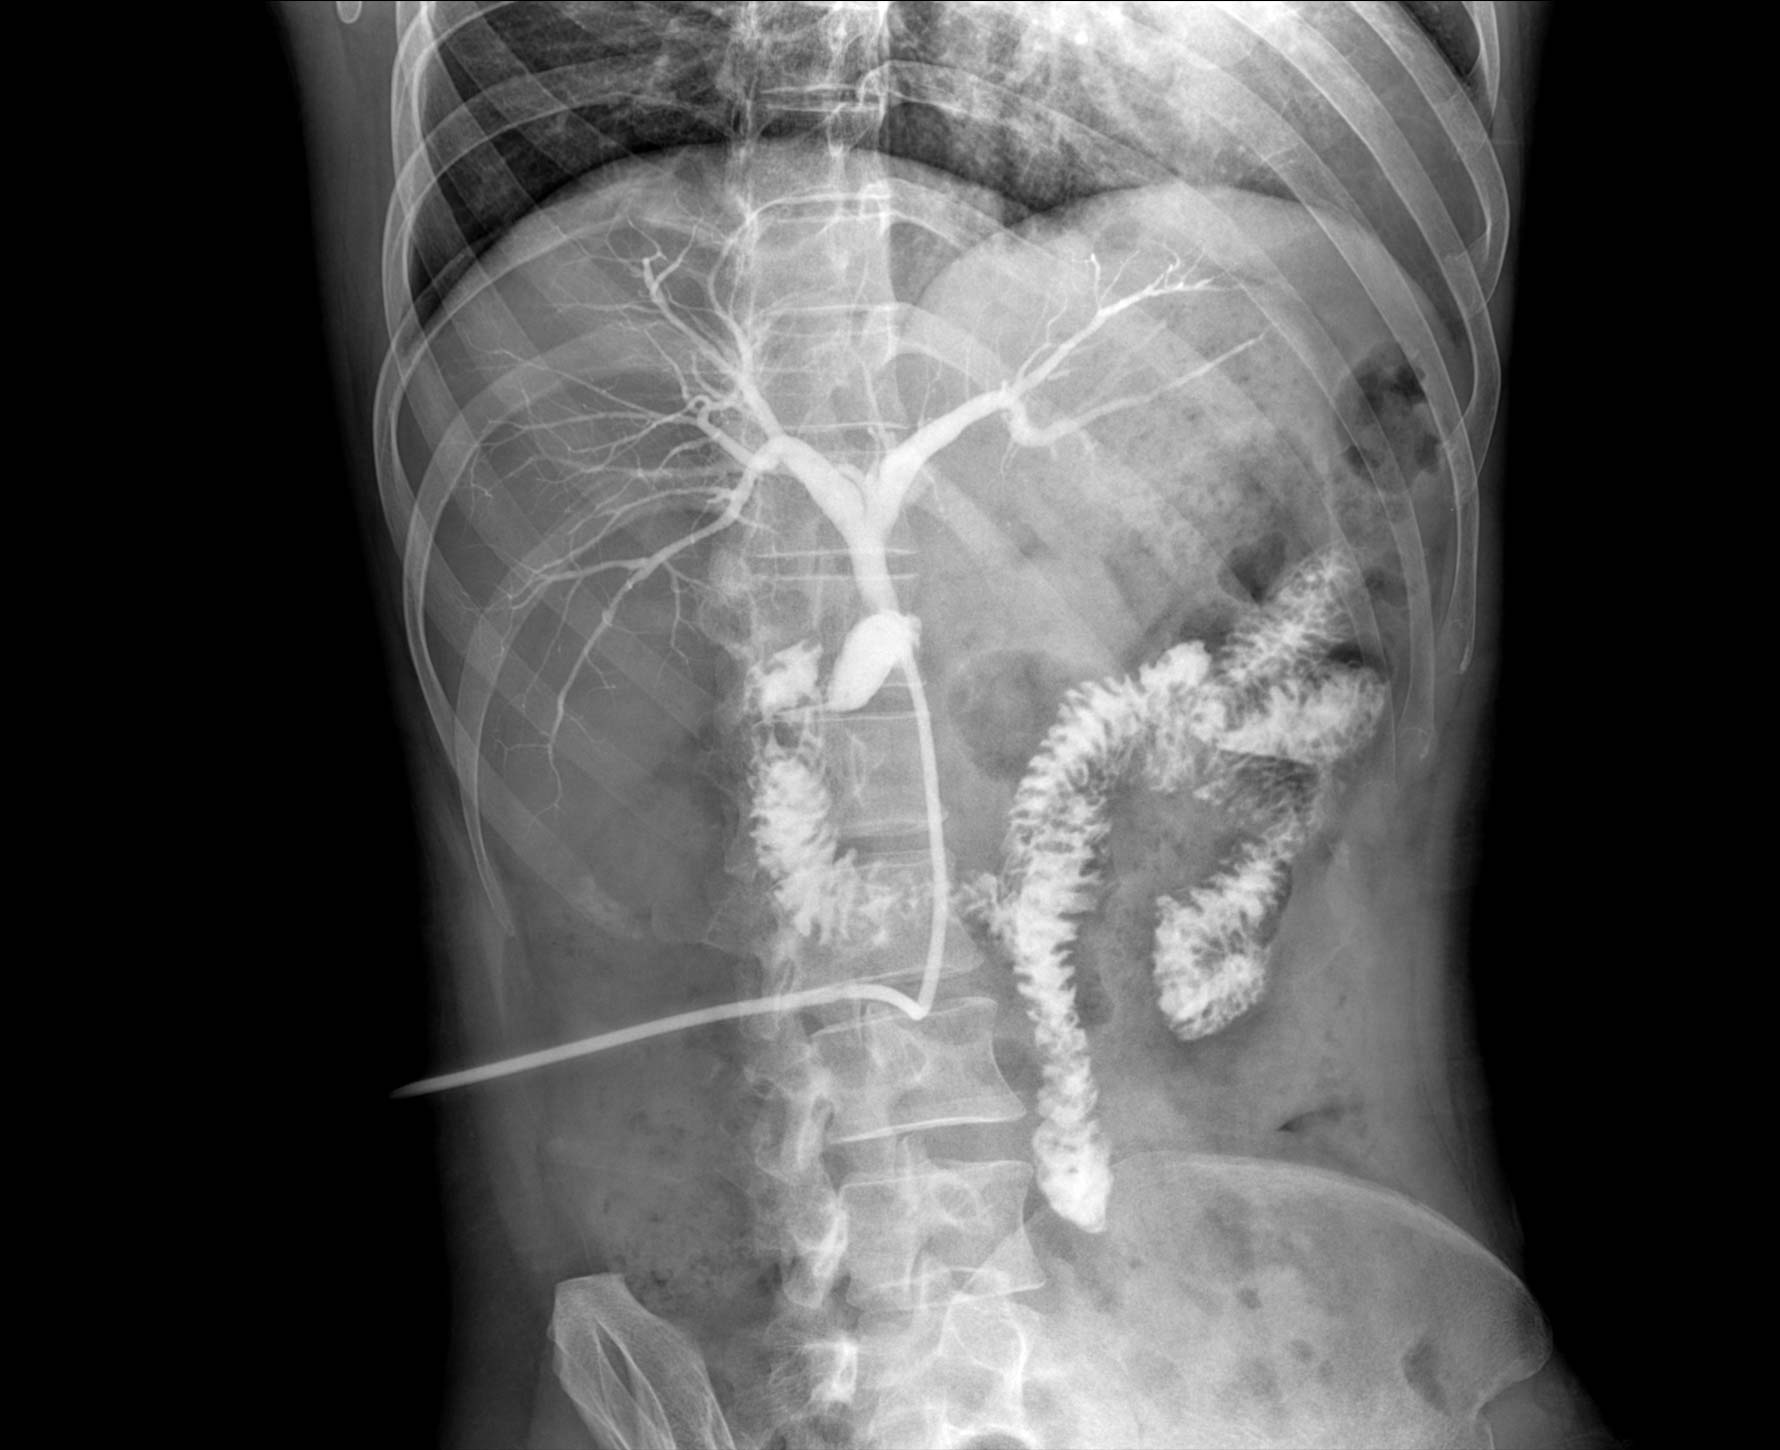

• 透视

适用于全身各

部位透视检查